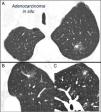

SPN is defined as a single, spherical, distinct, radiological opacity with a long axis of ≤30mm, primarily surrounded by aerated lung and without associated atelectasis, hilar enlargement or pleural effusion.1–3 SPNs may be observed on chest X-ray or chest computed tomography (CT) performed to study other diseases or for diagnostic screening for lung cancer (LC).3,6,7 Millimetric nodules (≤8mm in diameter)1,2,6 and subsolid nodules (SSNs)2,5 (Fig. 4), requiring different management,5–7 may be detected on CT (Fig. 1). SSNs include both ground glass nodules and partially solid nodules that combine a ground glass component with a solid component.2,5–7

Mixed subsolid solitary pulmonary nodule in the left upper lobe. Chest computed tomography with 2mm thin sections in a patient with a solitary pulmonary nodule in the left upper lobe. Axial slice (A) in upper lobes and coronal (B) and sagittal (C) reconstructions in the left upper lobe. An 18-mm ground-glass solitary pulmonary nodule is observed, with a 7-mm solid component in the interior. Resection by video-assisted thoracoscopy revealed adenocarcinoma.

Subsolid Pulmonary Nodule (5)These are ground-glass nodules, pure or with a solid component5 (Fig. 4). Determination of a subsolid nodule requires thin sections, preferably of 1mm, since small solid SPNs in 5-mm CT slices may appear as ground glass.2,5